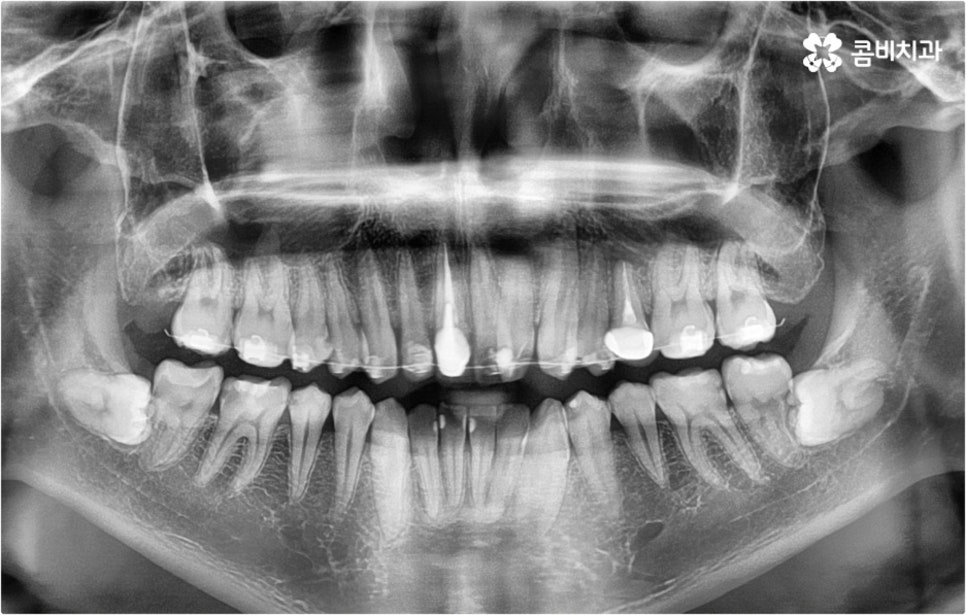

덧니의 원인에는 여러 가지가 있을 수 있으나 보통 혼합치열기, 즉 유치가 영구치로 교체되면서 둘이 공존하는 시기인 6~13세 사이에 교체가 원활하게 이루어지지 않는 것 (유치가 너무 빨리 빠져 충분한 공간 유지가 되지 않거나 너무 늦게까지 빠지지 않아 영구치와 겹쳐 나게 됨), 선천적으로 치아가 나올 공간이 부족하거나 영구치가 너무 크게 자라는 것 등을 원인으로 발생하는 경우가 많아 초등학교 고학년에서 중학교 저학년까지의 시기를 덧니교정 치료를 위한 정밀 검진의 골든 타임으로 여기고 있습니다.

덧니교정 시 환자분들의 상황에 따라 치아 이동에 필요한 공간이 부족하지 않다면 비발치 교정이 가능한데요, 이런 경우 치아 사이를 살짝 갈아서 여유 공간을 만드는 치간 삭제 방법, 마지막 어금니를 후방으로 이동시키는 방법, 그리고 악궁 확장 장치를 사용해 치아 사이를 벌려주는 방법 등 다양한 방법으로 공간을 만들어 치열을 가지런하게 바로잡아 줄 수 있습니다. 이때 환자분들의 구강 상태, 즉 악궁 크기 대비 치아의 크기, 치아가 겹친 정도, 덧니의 위치와 개수 등을 자세하게 검진한 다음 치아가 이동할 충분한 공간이 확보되지 않는다면 발치 교정을 하게 될 거예요.

아마도 많은 분들이 치아를 뽑는다는 것에 대한 두려움을 가지고 있으시겠지만 그렇다고 해서 발치 교정이 필요한 케이스임에도 불구하고 치아를 뽑지 않고 진행을 하게 되면 치아 이동이 생각했던 것만큼 이루어지지 않기 때문에 결과에 따른 만족감이 떨어질 수 있어요. 특히 부정교합의 정도가 심각하고 골격적인 원인이 영향을 주고 있는 경우에는 발치 과정이 불가피 할 수 있으므로 의료진과 충분하게 상담을 하셔서 자신의 현재 상황에 따른 발치 교정의 필요성을 정확하게 이해하고 치료를 받으시길 권유드리고 있습니다.

정밀 검진 후 상담을 통해 덧니교정 치료 계획을 자세하게 듣고 중간 중간 진행 과정에 대한 브리핑을 받는 등 담당의 선생님과 지속적으로 소통하게 된다면 1~2년 정도 비교적 오래 걸리는 기간 동안 보다 편안한 마음으로 치료에 임하실 수 있으실 거예요. 이를 위해 3D CT 같은 정밀 진단 장비를 갖추고 있는지, 처음부터 끝까지 의료진의 변화없이 책임 진료하는지 꼼꼼히 따져보고 치과를 선택하는 게 필요하다고 할 수 있어요.